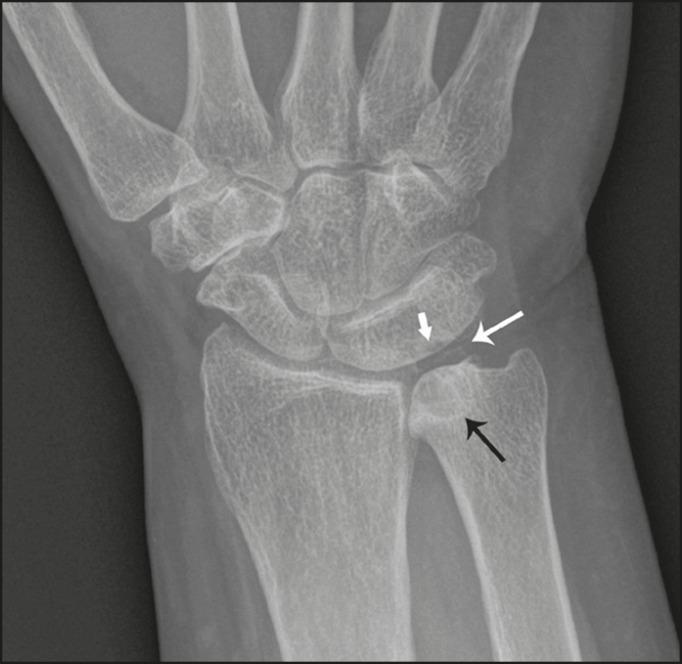

月三角联合与尺骨撞击综合征:图文综述

Lunotriquetral coalition and ulnar impaction syndrome: a pictorial essay.

Lunotriquetral coalition and ulnar impaction syndrome are among the spectrum of pathology encountered at the medial wrist. The co-existence of these entities in the same wrist is rare. The purpose of this pictorial essay is to present the etiology, clinical course, imaging findings, and treatment of lunotriquetral coalition and ulnar impaction syndrome, and co-existing disease.

月三角联合和尺骨撞击综合征属于腕关节内侧所遇到的一系列病理情况。这些病症在同一手腕中共存的情况较为罕见。本文通过图片展示的目的是介绍月三角联合和尺骨撞击综合征及其并存疾病的病因、临床病程、影像学表现和治疗方法。